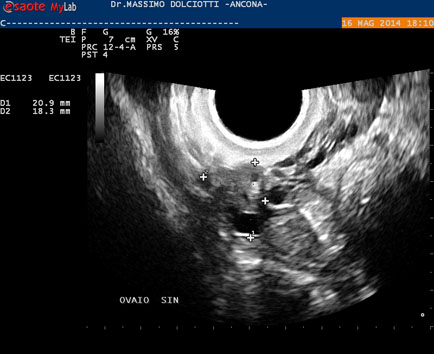

Data inserimento: 19 /05/2014Ecografia del: 16/05/2014 Strumento: Esaote MyLab 50 Gold - Responsabile Linea Cardio Esaote Regione Marche Dr. Franco Fabi Sonda: Endocavitaria Multifrequenza 4-8 MHz Età Paziente: F 27 anni Motivazione dell'esame: amenorrea. Beta HCG = 1.459 mUI/ml. Commento all'esame: le immagini ed il video documentano utero retroverso, con endometrio ispessito e presenza del sacco gestazionale delle dimensioni di 7,6 x 7,2 mm. All'ovaio destro presenza di corpo luteo gravidico con vascolarizzazione aumentata. Conclusioni: gravidanza alla quarta settimana di gestazione (Pregnancy at the fourth week of gestation). Potete esprimere le vostre osservazioni e commenti sul BLOG. Presentazione: Dr. Massimo Dolciotti - Ancona Elaborazione digitale: Andrea Dini - Ancona